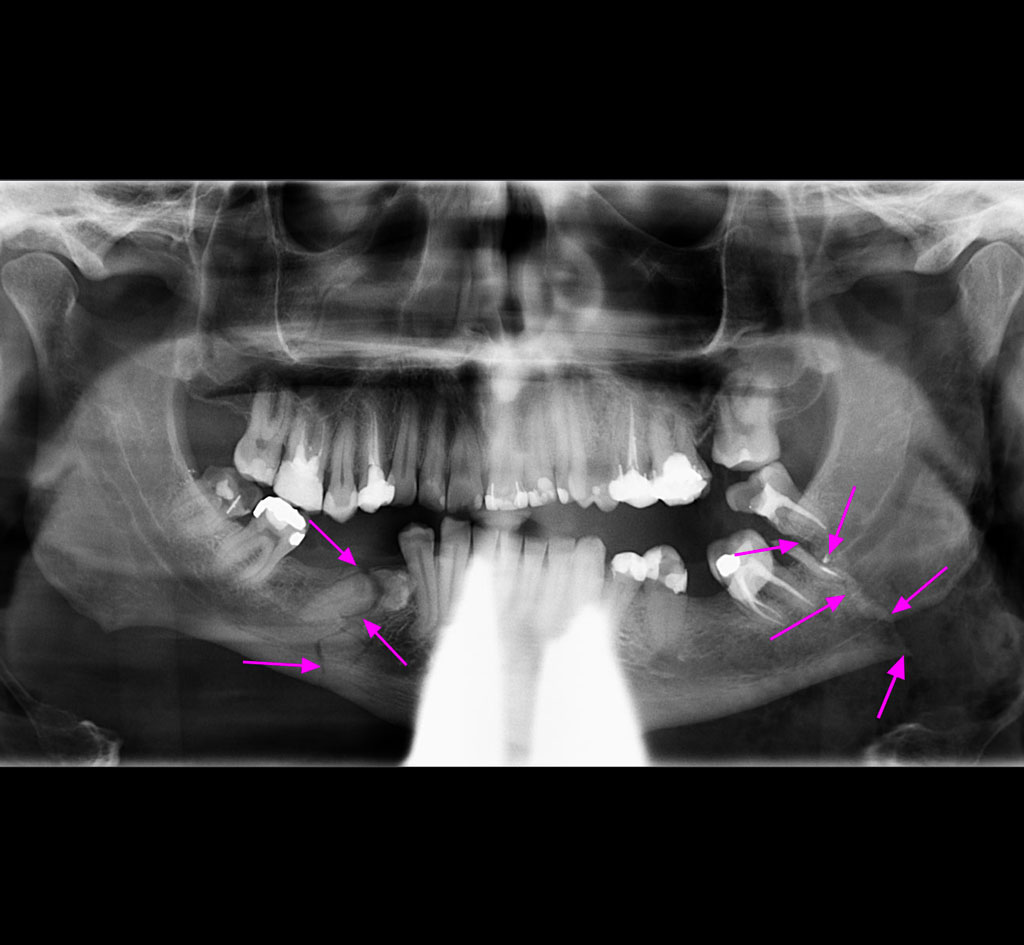

Les spécialistes en chirurgie buccale et maxillo-faciale ont la formation nécessaire pour traiter les patients ayant subi un traumatisme facial. La traumatologie maxillo-faciale comprend tout les types de fractures des os du visage, du front au menton, en incluant les plaies ou lacérations de la peau et des tissus mous, ainsi que les traumatismes dento-alvéolaires.

Les fractures les plus fréquentes sont celles de la mandibule (mâchoire inférieure), celle du tiers moyen du visage (maxillaire supérieur, os malaire, plancher de l’orbite).

La consultation initiale est généralement faite en milieu hospitalier. La chirurgie pour traiter les fractures est faite sous anesthésie générale. Une hospitalisation de courte durée est nécessaire dans la majorité des cas. Les cas plus complexes pourraient nécessiter une période d’hospitalisation plus longue.